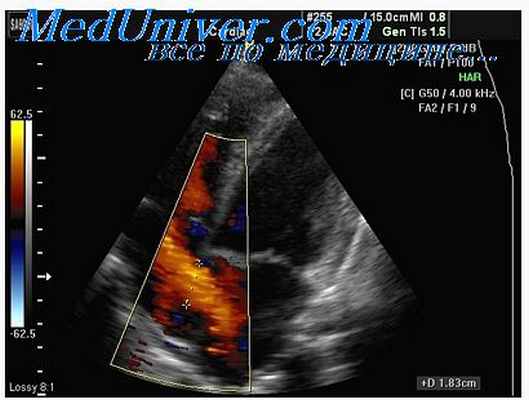

Легочный стеноз (ЛС) – сужение выносящего тракта правого желудочка, вызывающее препятствие току крови из правого желудочка в легочную артерию во время систолы. Легочный стеноз чаще всего бывает врожденным и протекает бессимптомно до взрослого возраста. Признаки легочного стеноза – нарастающе-убывающий шум изгнания. Диагноз устанавливают с помощью эхокардиографии. Больным с клиническими проявлениями и с большим градиентом требуется баллонная вальвулотомия.

Диагноз стеноз легочного ствола подтверждается проведением допплерэхокардиографии, с помощью которой можно оценить тяжесть заболевания следующим образом:

Легкая: пик градиента

Умеренная: пик градиента от 36 до 64 мм рт.ст. (пиковая скорость 3–4 м/с)

Тяжелая: пик градиента > 64 мм рт.ст. (пиковая скорость > 4 м/с)